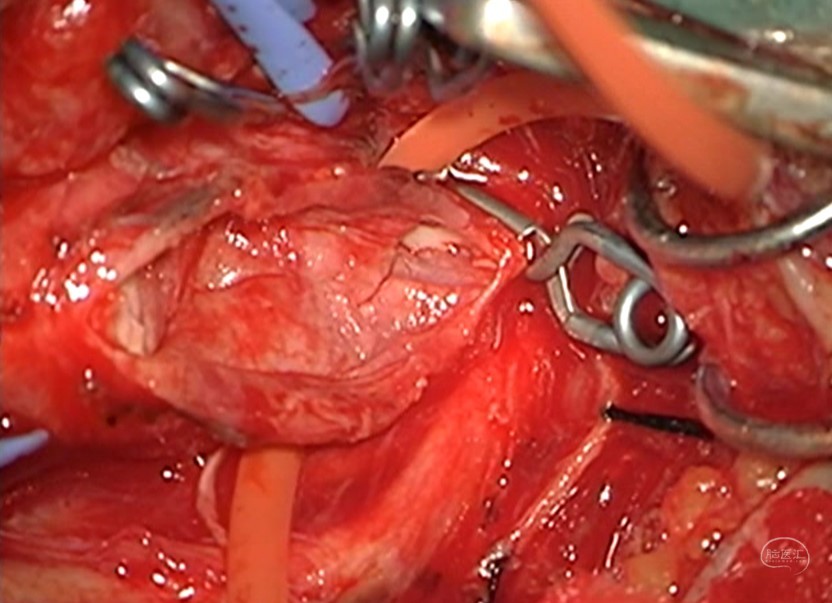

颈动脉内膜剥脱术